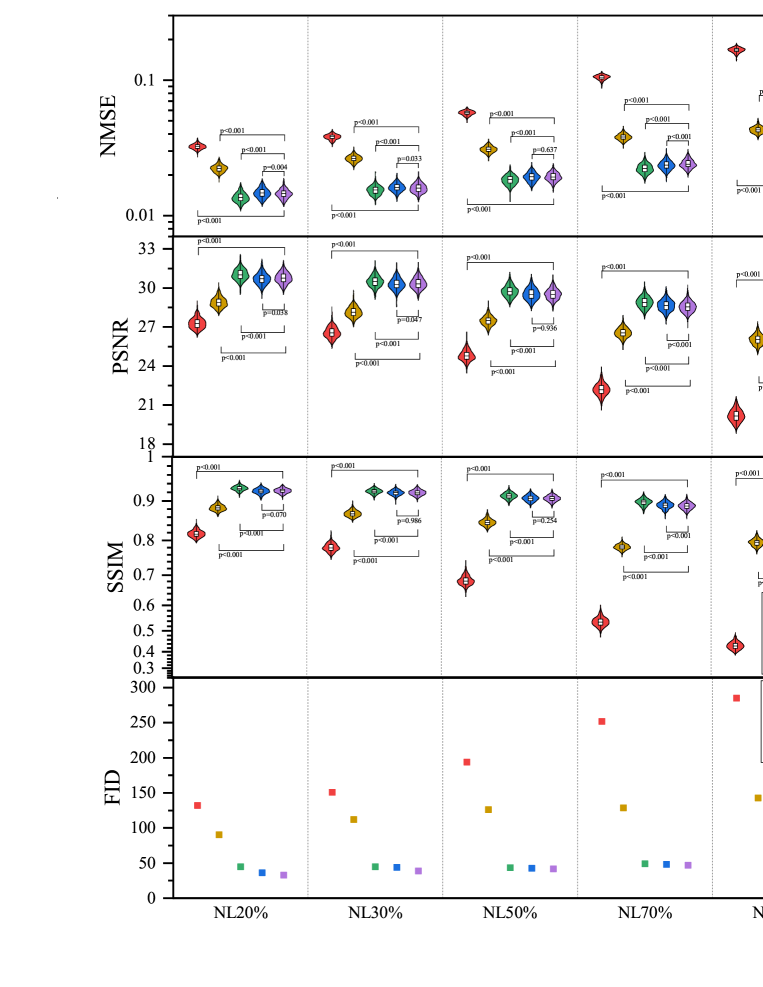

The testing results are shown in Table 1. Zero-filled image (ZF) is undersampled by a Gaussian downsampling trajectory. According to the comparison study results, the proposed method shows significant improvement for all test indicators compared with other methods. The FID of PIDD is significantly lower compared to PISD and nPIDD.

The testing result are shown in Fig. 7 and Fig. 8. Experimental results exhibit the same trend under all the different downsampling trajectories. The proposed method provides significant advantages for low downsampling percentage (high acceleration factor), with correspondingly significantly improved reconstruction quality.

All considered methods can restore image structure and edge information for low and medium noise levels (20–50%), with PIDD having strong advantages over PISD and nPIDD. This advantage weakens as noise level increases, and PISD, which focuses on overall information recovery, performance slightly surpasses PIDD, which focuses more on edge information preservation, for high noise (70–80%).

Fig. 12 shows NMSE, SSIM, PSNR and generator loss (G Loss) of the four groups changing with the training process, and Fig. 13 shows testing examples with respect to different epoch weights.

Models with GR (GRLR, GRnLR) have faster convergence and better final results compared with those without GR (nGRLR, nGRnLR). If the model applies GR, then using LR has little further impact effect on the results. For non-GR models, nGRLR converges significantly slower than nGRnLR but final results are superior. Therefore, we chose GRLR as the generator for subsequent study.